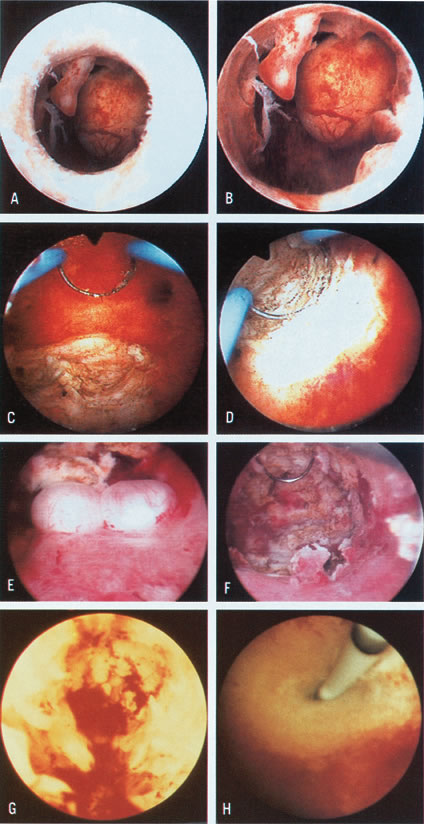

Although large endometrial polyps, particularly when pedunculated, are easily removed by hysteroscopic guidance, the removal of submucous leiomyomas requires more experience. Several methods are available. When the leiomyoma is smaller than 2 to 3 cm and is pedunculated, mechanical transection of the pedicle expedites its removal. Nonetheless, myomas larger than 3 cm with thick pedicles, or sessile myomas, must be removed by segmental shavings with a resectoscope and a cutting loop. This is performed systematically until the uterine wall is reached, when resection should stop. With experience, the endoscopist learns tactile appraisal provided by the resecting loop to distinguish fibrous myomatous tissue from myometrium. In addition, he or she can visually appraise the fibrotic tissue and the fascicularis aspect of the myometrium. When myomas penetrate deeply into the uterine wall, laparoscopy should be considered to monitor the hysteroscopic-resectoscopic operation transabdominally (Color Plate 1A to F; Figs. 21, 22, 23, 24, 25, and 26).8–17

Color Plate 1. A. Endometrial polyp and submucous myoma, as seen just before crossing the internal os. B. Closer view of endometrial polyps and pedunculated submucous myoma. C. Resection of posterior submucous myoma. D. Selective coagulation of the myoma bed after resection. E. Small submucous myomas in the posterior uterine wall. F. Hysteroscopic view after resection of posterior submucous myomas. G. Hysteroscopic view after initial treatment of severe intrauterine adhesions completely occluding the uterine cavity. The remaining fibrotic stumps on lateral walls are visible. H. Hysteroscopic ostial tubal cannulation using a 1-mm OD catheter.